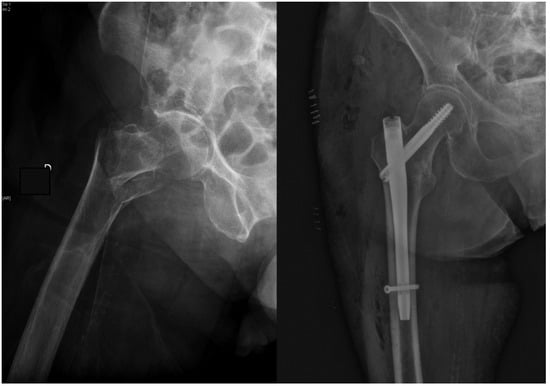

Treatment of Trochanteric Hip Fractures with Cephalomedullary Nails: Single Head Screw vs. Dual Integrated Compression Screw Systems

| Cut-out | 8 (2.1%) | 2 (0.8%) | 6 (4.8%) | 0.016 |